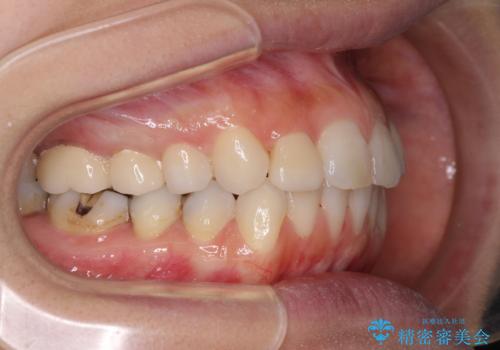

- 前歯のデコボコと矮小歯、更には痛みを感じる奥歯のむし歯を気にして来院された患者様です。

奥歯には根管治療が必要な歯があり、上顎側切歯は左右ともに矮小歯でした。

上下前歯のデコボコはワイヤーでもインビザラインでも対応可能でしたが、補綴治療が多く必要となることから、インビザラインでの矯正治療を行いながら、並行して補綴治療を行うこととしました。

まずは根管治療を行った上で矯正治療用の仮歯を装着し、矯正治療後半に補綴治療を並行して行うこととしました。